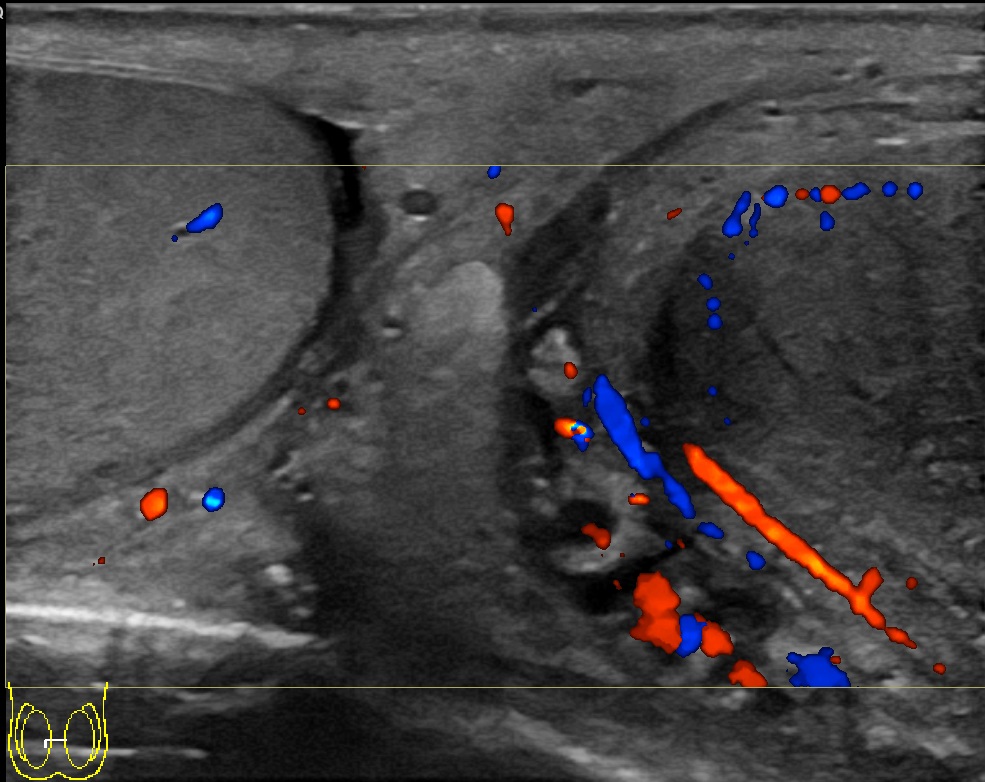

혈액 검사에서 적혈구 침강 속도(ESR) 수치가 증가하는 것이 확인된다.[1] 소변 검사를 통해 균 배양 검사 및 감수성 검사를 실시한다.[1] 초음파 검사를 통해 진단할 수 있다.[1]